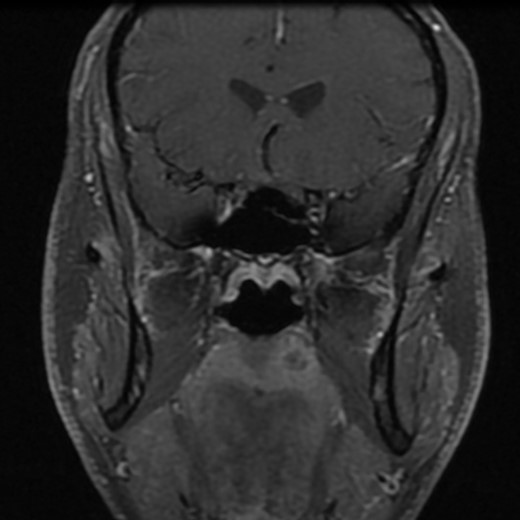

A 37-year-old patient with no smoking or drinking history was referred to our oncology clinic in November 2012 for an SCC of the left palate. The lesion consisted of a 1-cm erythematous nodule of rubbery consistence. The rest of the examination was normal. A computed tomography scan confirmed a 13 × 11 mm lesion of the left soft palate without radiological evidence of deep invasion. The possibility of a minor salivary gland tumor was considered and a magnetic resonance imaging (MRI) scan was requested. A second biopsy was performed and the original pathology slides were reviewed. Both specimens suggested an SCC. The MRI scan revealed a submucosal lesion without any signs of local infiltration (Fig. 1). No regional disease was found. The lesion was staged as a T2N0 SCC of the buccal cavity and a curative oncologic surgery was proposed to the patient. Partial resection of the soft palate, maxilla and medial pterygoid plate with supracentimetric margins was undertaken as well as an ipsilateral selective neck dissection of levels 1–3. Closure of the deficit was with a fasciocutaneous antebrachial free flap and a prophylactic tracheostomy was performed. There were no complications. The tracheostomy was removed and the patient started eating on Day 7. He was discharged from the hospital on Day 8.

Post-gadolinium T1-weighted coronal section showing the lesion on the palate.